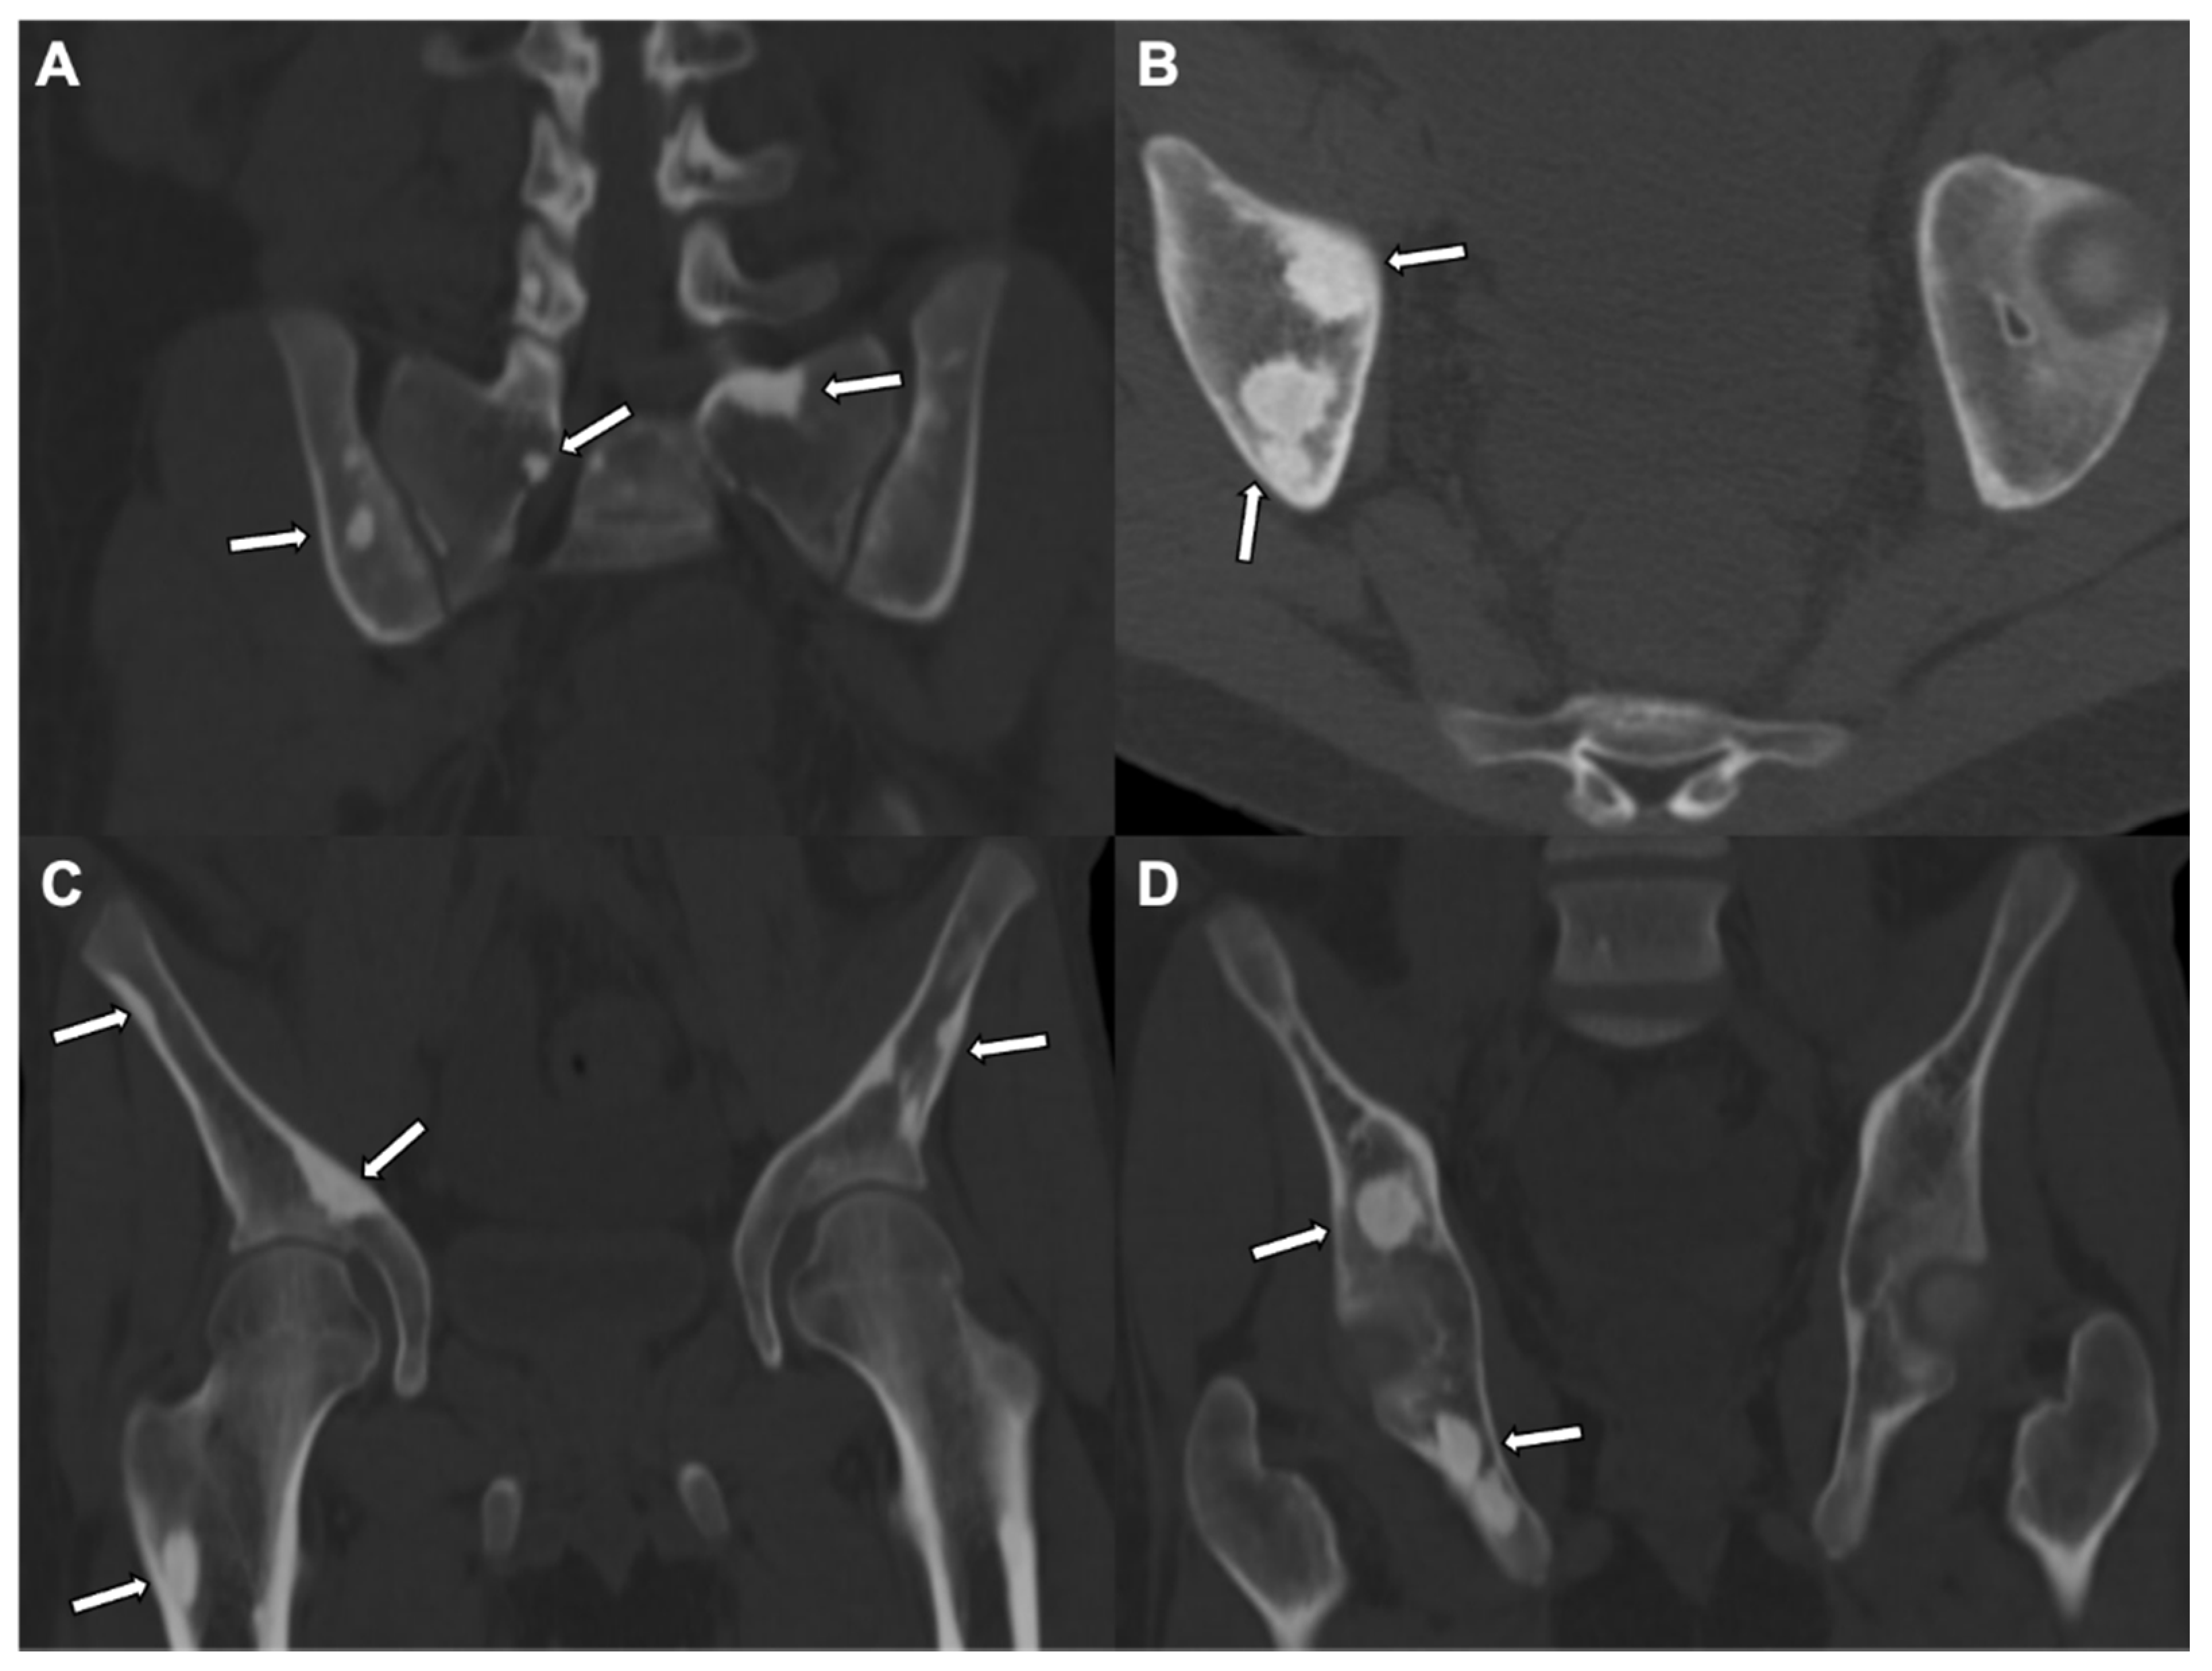

4. Enostosis (Bone Island)

- Ulano, A.; Bredella, M.A.; Burke, P.; Chebib, I.; Simeone, F.J.; Huang, A.J.; Torriani, M.; Chang, C.Y. Distinguishing Untreated Osteoblastic Metastases From Enostoses Using CT Attenuation Measurements. Am. J. Roentgenol. 2016, 207, 362–368. [Google Scholar] [CrossRef] [PubMed]

- Bernard, S.; Walker, E.; Raghavan, M. An Approach to the Evaluation of Incidentally Identified Bone Lesions Encountered on Imaging Studies. Am. J. Roentgenol. 2017, 208, 960–970. [Google Scholar] [CrossRef]

- Sala, F.; Dapoto, A.; Morzenti, C.; Firetto, M.C.; Valle, C.; Tomasoni, A.; Sironi, S. Bone islands incidentally detected on computed tomography: Frequency of enostosis and differentiation from untreated osteoblastic metastases based on CT attenuation value. Br. J. Radiol. 2019, 92, 20190249. [Google Scholar] [CrossRef] [PubMed]

- Hong, J.H.; Jung, J.-Y.; Jo, A.; Nam, Y.; Pak, S.; Lee, S.-Y.; Park, H.; Lee, S.E.; Kim, S. Development and Validation of a Radiomics Model for Differentiating Bone Islands and Osteoblastic Bone Metastases at Abdominal CT. Radiology 2021, 299, 626–632. [Google Scholar] [CrossRef] [PubMed]

| Radiographic/CT features | Juxtacortical, well-circumscribed homogenous sclerotic lesion | Homogenous intra-medullary sclerotic focus with spiculated margins | Small (less than 2 cm) cortical lucency with extensive surrounding sclerosis | Expansile large (more than 2 cm) lucent lesion with matrix mineralization |

| Treatment | None if asymptomatic; excision if complications related to mass effect | None | Percutaneous CT guided radiofrequency ablation | Surgery or percutaneous CT guided ablation |